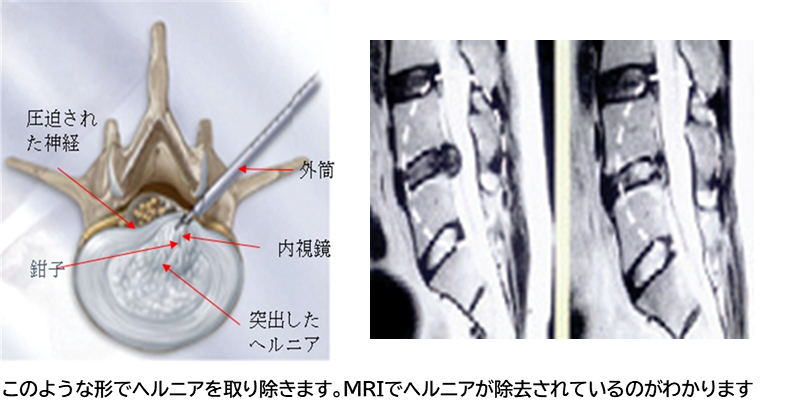

細い内視鏡や専用の高周波メスを用いることで、約8mmの皮膚切開で手術を行うことが可能になりました。ヘルニアの存在する場所の皮膚を切開し、 直径7mmの筒を挿入し、内視鏡で椎間板を観察しながら椎間板ヘルニアを摘出します。術前の患者様の症状によりますが、術後3時間から歩行開始し、 翌日退院が可能です。